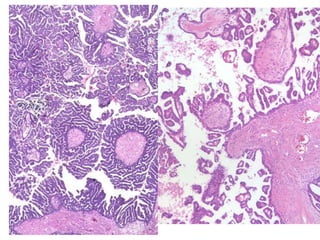

Hiperplasia complexa com atipias / Neoplasia intraepitelial endometrial (EIN)